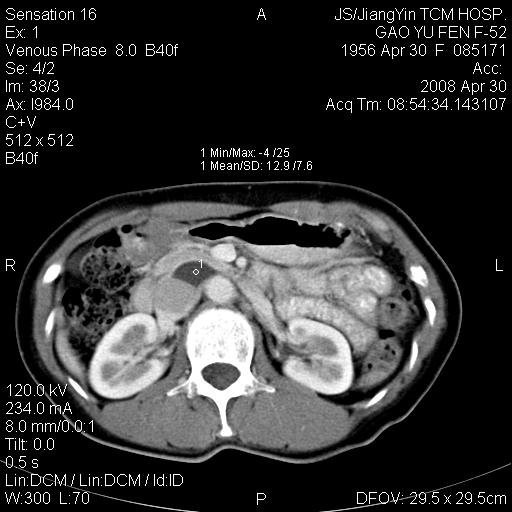

标题: CT13307:肠系膜囊肿? [打印本页]

标题: CT13307:肠系膜囊肿?

囊性淋巴管瘤可能比较大。

良性囊性占位,来源于肠系膜的可能性大

病变位于肾静脉后方,支持腹膜后占位性病变,以囊性淋巴管瘤可能性大.